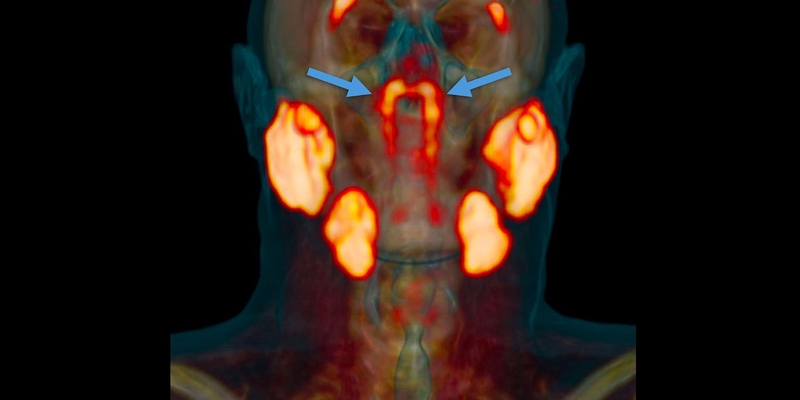

Neįtikėtina – mokslininkai žmogaus galvoje surado naują organą